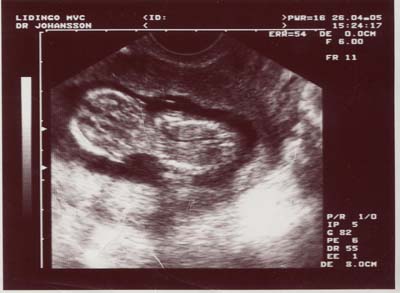

Ultraljud

v 12

Här togs ett tidigt ultraljud för att se hur gammal jag var eftersom mina föräldrar inte visste det. De trodde att jag nog var ca 6-7 veckor, men enligt beräkningarna så var jag redan ca 10 veckor (i v 12). Hoppsan!